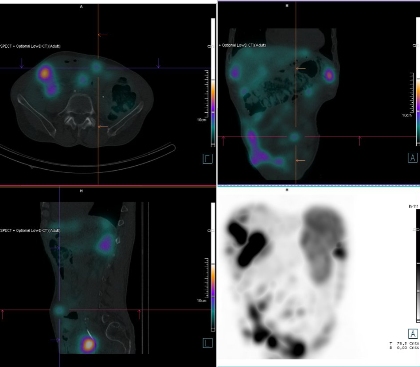

2: Fúze SPECT/CT břicha a pánve 4 hod. po aplikaci OctreoScanu.

/

/ Obr. č. 3: Fúze SPECT/CT břicha a pánve 4 hod. po aplikaci OctreoScanu.

Pozorujeme patologicky zvýšenou depozici radiofarmaka: nejméně čtyři ložiska v pravém jaterním laloku (ložisko s vysokou akumulací laterálně, největší ložisko vysoce akumulující oválného tvaru dorzokaudálně, další dvě malá dorzolaterálně a kraniálně), vícečetná drobná ložiska v břiše a pánvi, zřejmě v uzlinách mezenteria a na peritoneu, ložisko pod dolním okrajem sleziny.

Akumulace dále ve slezině, ledvinách a střevních kličkách představuje fyziologickou distribuci. Vedl. nález obrovská hydronefróza pravé ledviny bez akumulace.

Mnohočetná ložiska patol. depozice Octreotidu odpovídají generalizaci procesu v dutině břišní - játra, mezenterium, karcinomatoza peritonea, pod slezinou.